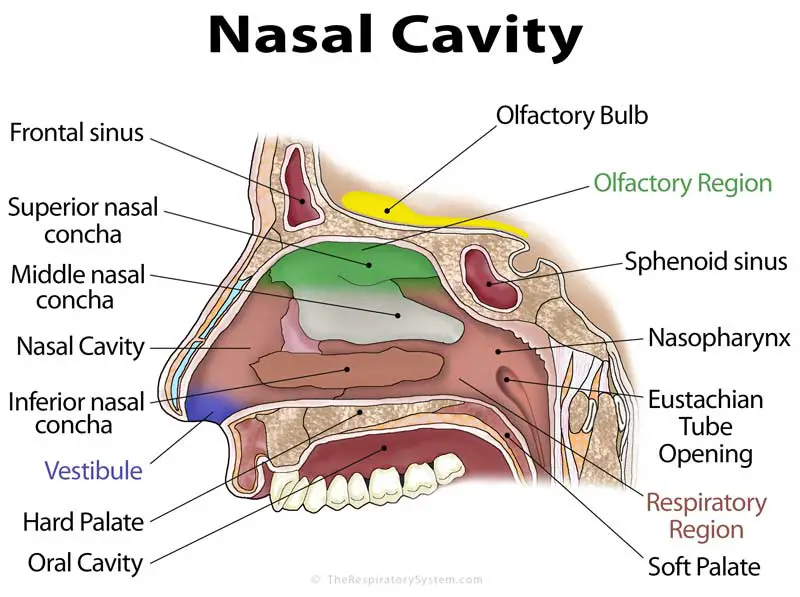

Projecting out of the lateral walls of the nasal cavity are curved shelves of bone. The flow of air from outside of the body to the lungs begins with the nose which is divided into the left and right nasal passages.

Just beneath each concha is a passage known as the meatus named for the adjacent turbinate.

The lateral nasal wall consists of inferior and middle turbinates and occasionally a superior or supreme turbinate bone. The turbinates consist of three ridges of thin shell like bone known as the nasal conchae. The nasal passages are lined with a membrane composed primarily of one layer of flat closely packed cells called epithelial cells.

Superior middle and inferior meatus. The nasal cavity extends from the external opening the nostrils. The nasal cavity is surrounded by a.

In bones behind your nose are your sphenoid sinuses. Anatomy of the nasal cavity. This region is divided into a labyrinth of slit like passages by multiple bony proturbances that fill the nose and act as shelves.

The exhaled air travels in the reverse path and leaves the body through the nasal cavity. The superior the middle and the inferior turbinates. Theyre lined with soft pink tissue called mucosa.

Role as a passage for inhaled air. Normally the sinuses are empty except for a thin layer of mucus. The ridges are named for their position.

Internally the nasal septum divides the nasal cavity into a right and left side. They connect to your nasal passages in a complex network of air flow and drainage passages. One of the functions of the nose is to drain a variety.

During inhalation air enters through the nostrils and passes via the nasal cavity into the pharynx and larynx the next sections in the respiratory tract to eventually reach the lungs. Anatomy and physiology of the nasal cavity inner nose and mucosa introduction. Anatomy of the nose.

The external nose consists of paired nasal bones and upper and lower lateral cartilages. The nasal cavity refers to the interior of the nose. The nasal cavity is the most superior part of the respiratory tract.